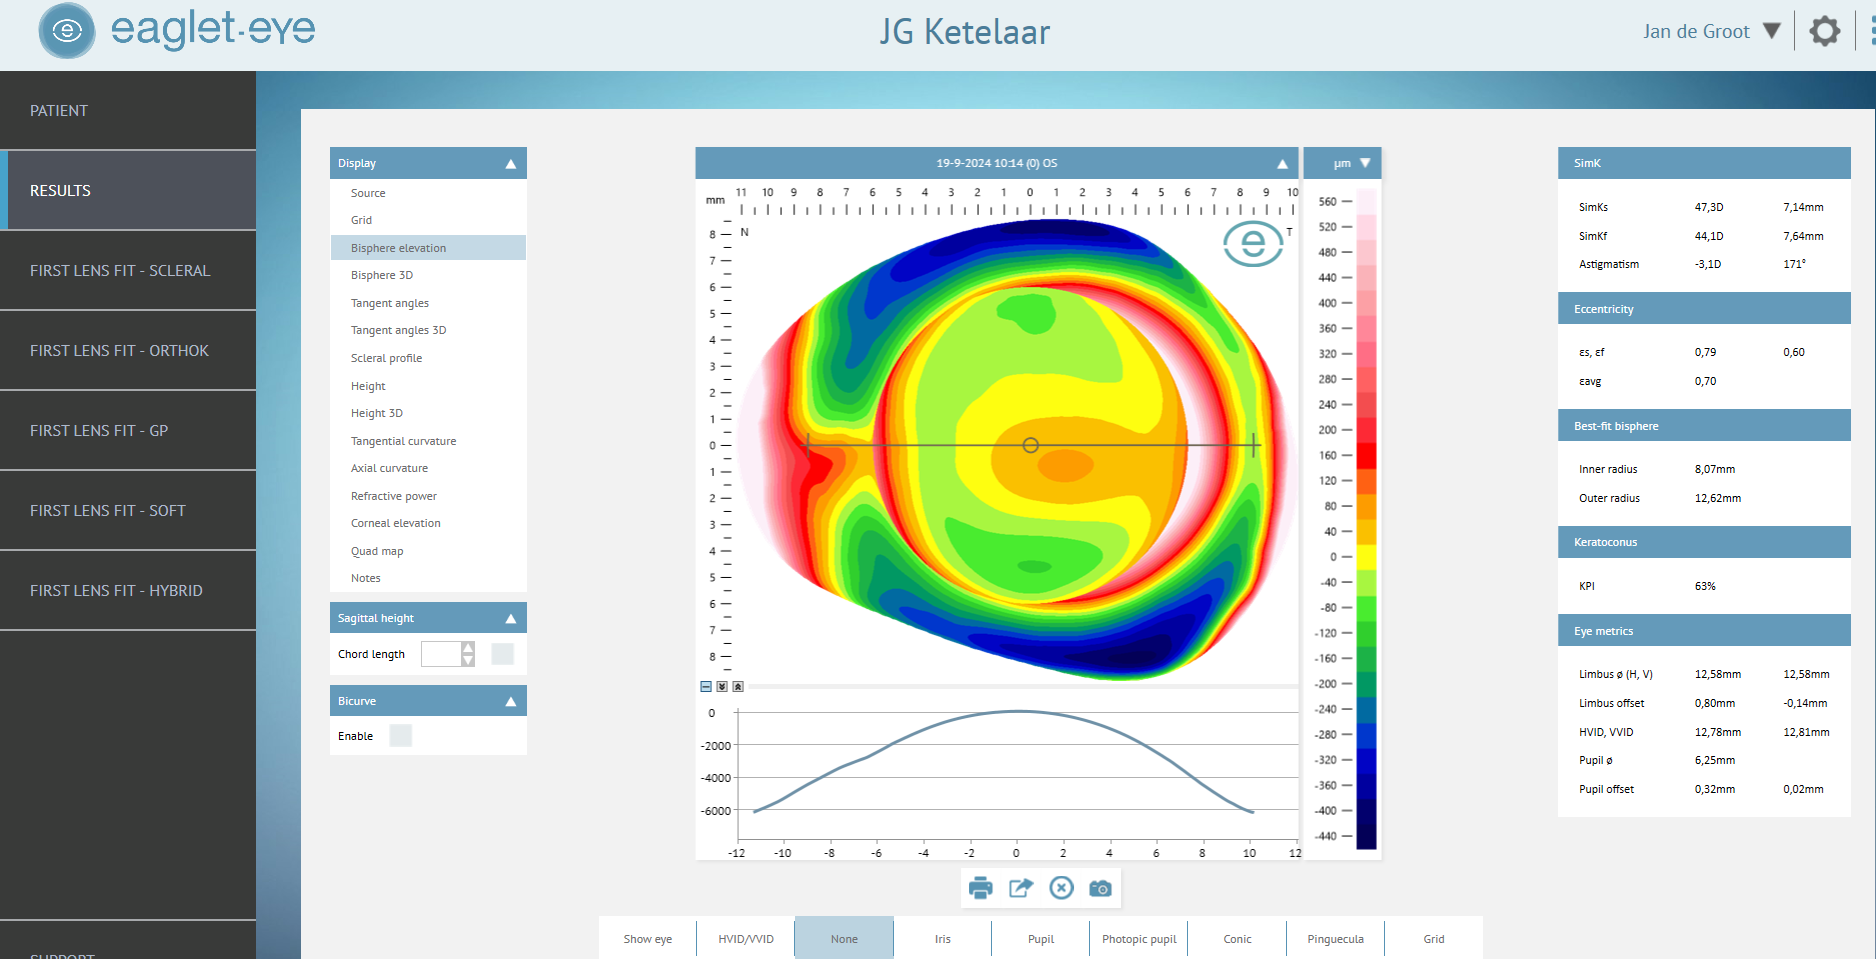

JGK gebruikt de Eye Surface Profiler (ESP) voor nauwkeurige opmeting van het oogoppervlak — inclusief het oogwit tot op 20 mm — als basis voor alle medische lensaanpassingen.